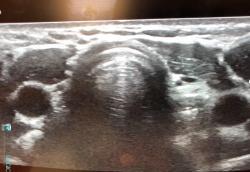

18 yr old for USG neck- Altered thyroid funtion See more

Lingual thyroid( ectopic thyroid) with secondary colloid goiter changes See more